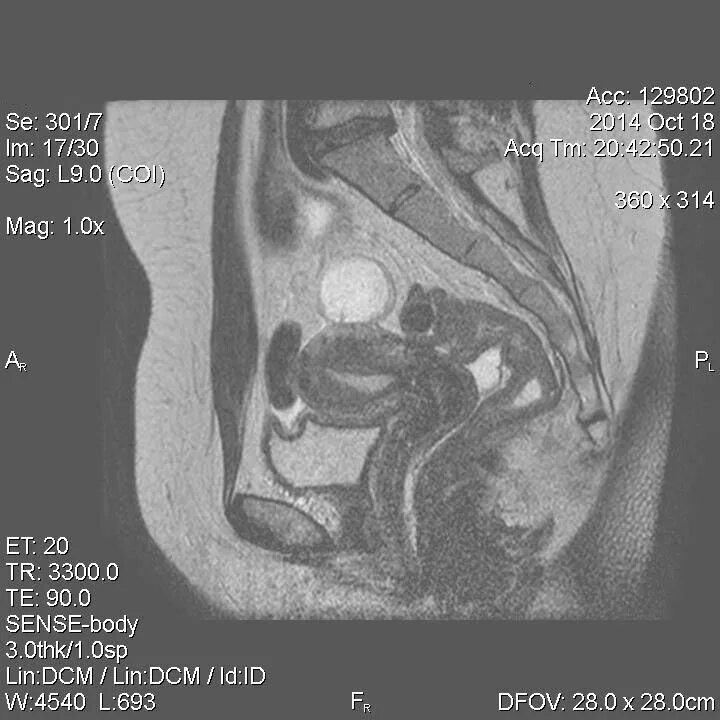

Инволютивные изменения органов малого таза это